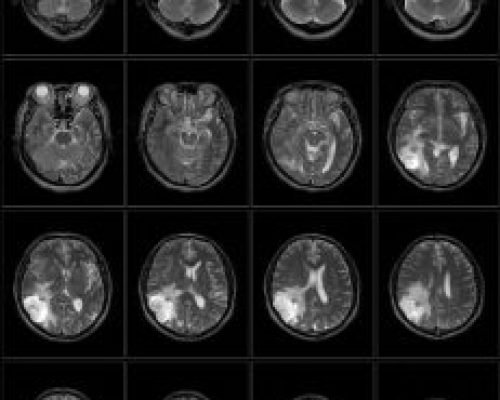

The PICA MRI system is our flagship product with its unique open architecture, advanced hardware platform and leading-edge clinical applications make it ideally suited for patient comfort, fast acquisition times and excellent image quality. The PICA has passed all ACR Accreditation requirements of 4 MRI modules: Head, Spine, Body and MSK. This accreditation also means that patient scans from PICA is approved for financial reimbursement by the US Government MEDICARE program as well as private insurance companies in the US.

The PICA’s 20-minute MRI exam of the Brain scan is an example of our commitment to delivering value, performance, and innovation.